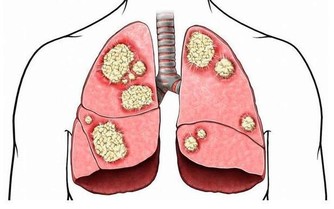

他們發現這顆腫瘤是從其中一個卵巢開始成形,再慢慢移到她的腹腔。

現在醫生也終於能夠親眼目睹這顆重達132磅( 約60公斤 )的腫瘤,

幾乎是普通成年女性的體重,而且也只比Talamantes的體重輕4公斤而已!

她的醫療團隊認為這是有史以來最大的卵巢腫瘤,也是第一次看到這麼大的腫瘤。